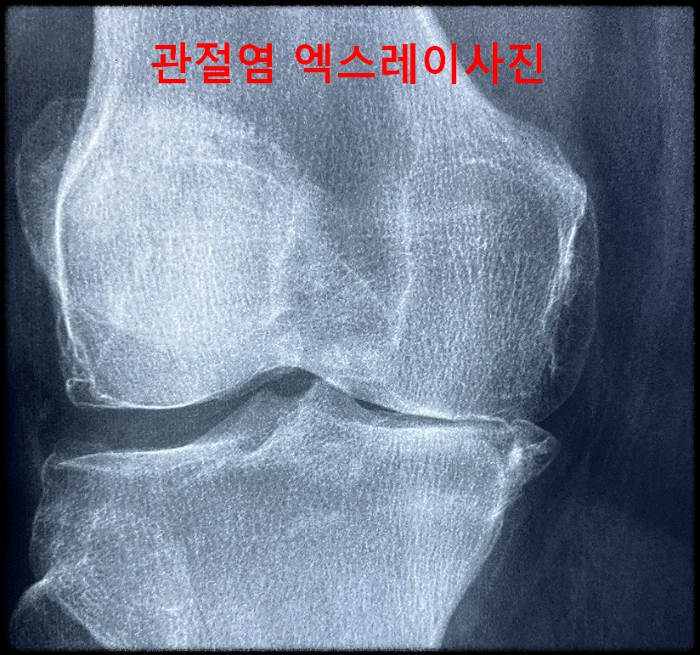

▶나이가 들었다고 생각할 때 제일 먼저 나타나는 증상은 무릎통증과 관절마디마디가 아프다는 이상신호를 보내기 시작하면서 계단이 점점 두려워지고 심해지면 걷는 등의 일상적인 것도 힘들어지게 된다.

▶연골은 우리가 흔히 알고 있는 물렁뼈로 사람의 뼈 중에 연한 뼈로 무릎이나 팔꿈치등에 관절과 관절 사이에 연결 부분에 있으며 모든 뼈와 뼈사이에 존재하고 있습니다.

따라서 뼈와 뼈사이를 보호하는 보호막으로 이 보호막이 관절 안에서 잘 버티고 있느냐에 따라서 관절의 건강도를 알 수 있다. 연골의 아래와 같이 3가지로 구성되어 있다.

①관절통증완화: 관절의 염증반응을 억제하고 연골 세포의 파괴를 방지하는 효과가 있습니다. 연골은 나이가 들어갈수로 석회화가 진행되는데 프로테오글리칸은 이를 지연시키는 역할을 하는 것입니다.

②무릎통증완화: 특히 연골사용이 제일 많은 무릎통증완화에도 크게 도움이 됩니다.